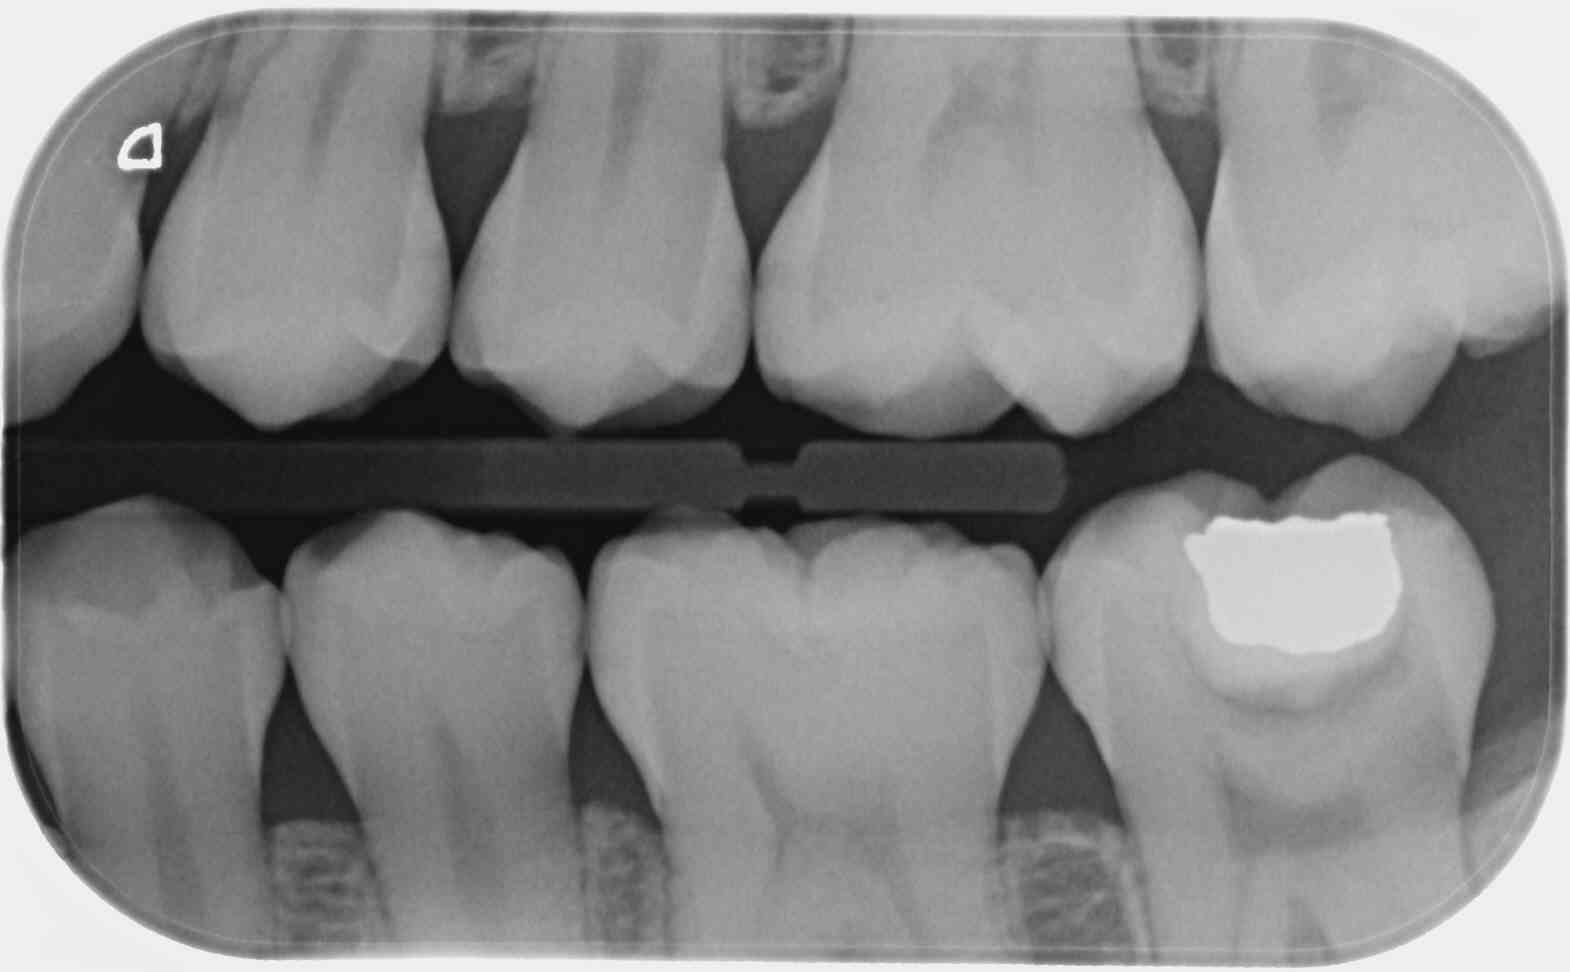

Sur un film 3+ je vois toutes les couronnes de la 7 a la 3... si je fais bite wing gauche et droit ca fait 20 couronnes, je peux compter combien de secteurs ?

C'est une faille de la CCAM qui permet, avec un peu de mauvaise foi, de coder 4 secteurs avec seulement 2 clichés, le nombre de clichés n'étant pas précisé dans le libellé.

1 radio (au singulier) en bite-wing secteur 1 et 4 = 7.98€ (HBQK389, 2 secteurs mais 1 seul cliché)

2 radioS (au pluriel) en bite-wing secteurs 1, 2 , 3 et 4 = 31.92€ (HBQK443, 4 secteurs, plusieurs clichés sans précision sur leur nombre).

T'es con d'utiliser des films taille 3 surtout avec des CDC de bonne composition. ca fait que 2 secteurs ou 4. Alors que 4 clichés ca fait 4 secteurs....ou 8. Les rétro alvéolaires sont offertes. -)

Le problème vois tu avec ces films étendus c'est que moins tu as de clichés moins tu as de dents au centre d'un cliché et moins tu as de secteurs. -)))